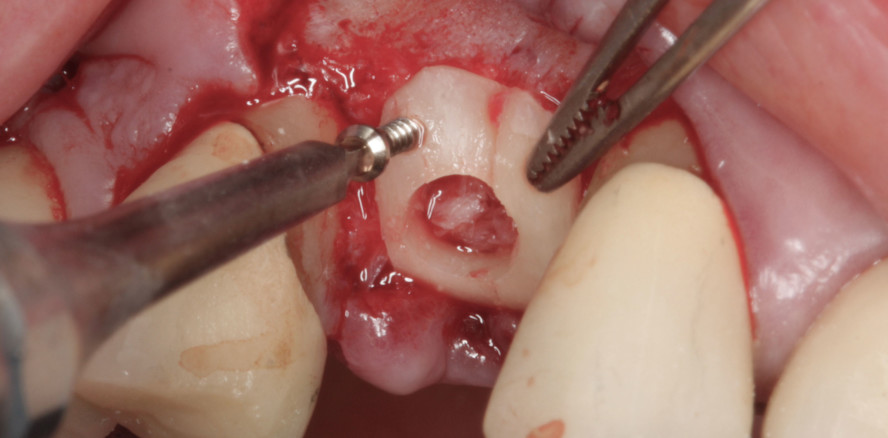

Das chirurgische Protokoll sieht bei der sog. Hangar-Technik vor, dass die okklusale Schale nach der Fixierung mit Osteosyntheseschrauben mittels einer Trepanfräse – möglichst in gleichem Durchmesser wie das Implantat – durchstoßen wird, sodass in der Folge das Implantat durch diese Trepanationsöffnung inseriert werden kann. Zuvor wird der Zwischenraum mit autologen Partikeln gefüllt.

Die 61-jährige Patientin stellte sich mit einem nicht erhaltungswürdigen Zahn 14 im Oberkiefer rechts vor. Ziel der geplanten Behandlung war die adäquate Rekonstruktion des Hart- und Weichgewebes sowie die prothetische Neuversorgung mittels einer implantatgetragenen Krone. Danach erfolgt die Rekonstruktion des Knochendefekts, wobei eine zuvor entnommene Knochenschale entsprechend der Schalentechnik nach Prof. Khoury auf Distanz gesetzt und mit kleinen Osteosyntheseschrauben fixiert wird.

Im vorliegenden Fall konnte dank der Hangar-Technik das Einbringen des Implantats zeitgleich mit der Rekonstruktion des vertikalen Defizits erfolgen. Bei der „Hangar-Technik“ kann das Implantat simultan mit der vertikalen Knochenaugmentation durch die okklusal fixierte Knochenschale inseriert werden.